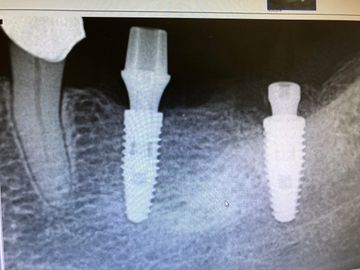

The implant and Healing abutment have bone growth up and around the Healing abutment on a 3.0 platform. reviewing abutment with tissue model removed on model there's abutment material all the way out to edge of implant. IT WILL NEVER SEAT!

This will never seat in the mouth, blanch tissue or get hung up on bone and not seat.

instead choose 1.5 or 2.5 margin on abutment, build out emergence from platform better.